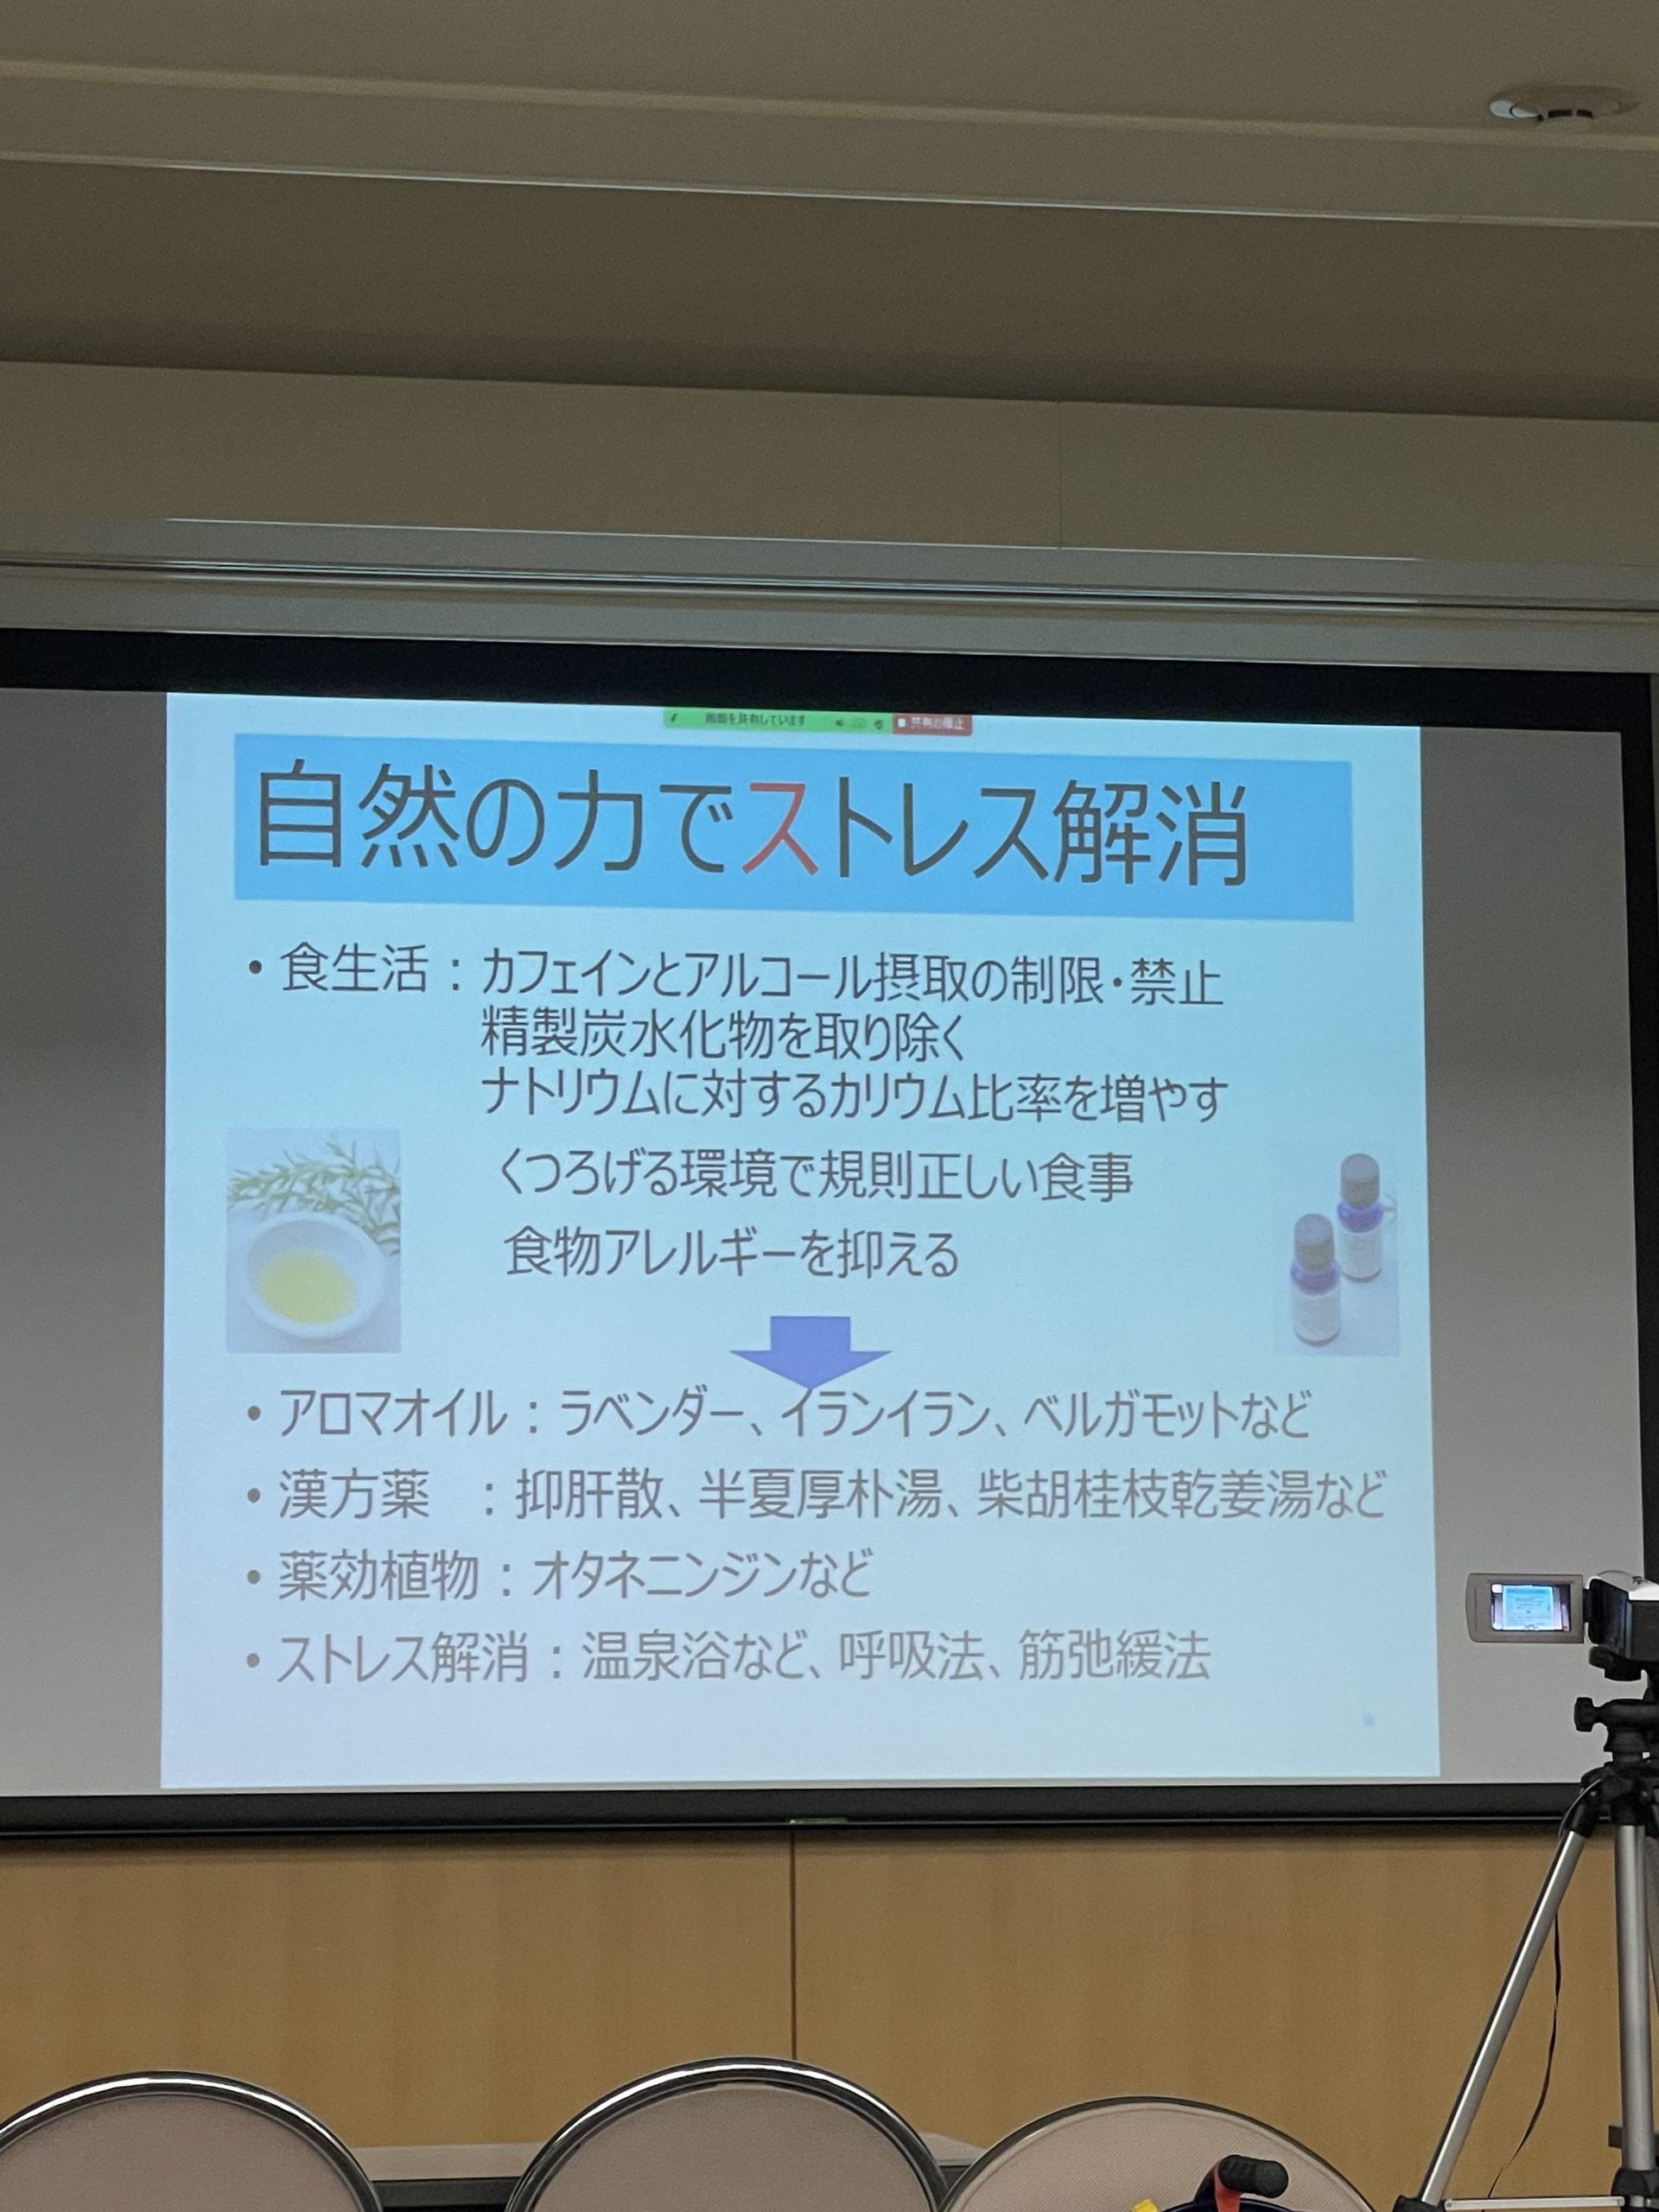

メディカルアロマ外来 2022.3.1

医療に使われるアロマを取り入れております。

フランスやベルギーでも現在、医療として使われておりアメリカでも取り入れを始めています。

市場に出回っている一般的なエッセンシャルオイルの多くはその純度が証明されていなくて、全てが安全というわけではありません。

増量剤などの添加物や農薬などの残留物、不純物が含まれていることがあります。

クリニックで取り扱っているアロマオイルはドテラ社のものでCPTG基準を満たした最高級の品質です。

経口摂取もできますし原液塗布もできます。

院内はその日のお天気、患者様の気分に合わせてブレンドしてディフューザーで空間に噴霧しております。

デンタルエステにも顎回りから首筋にかけて患者様の症状によってオイルを使い分けますし、ホワイトニングの患者様には御希望でしたらアロマオイルを使ったハンドマッサージも行っております。

患者様によっては1瓶を買われる方もいらっしゃいますが小さい携帯瓶に2,000円(税抜)で調合しますのでぜひお声かけ下さい。

歯科でも漢方薬が処方できるんです 2022.2.1

2022年2月13日「日本歯科東洋医学会学術研修会」に行ってきました。

以前のマンスリーブログでも紹介しましたが、歯科でもあれから4種類増えて11処方ができるようになりました。

漢方薬治療も鍼灸治療もできますが、今回は漢方薬についてお話致します。

日本歯科医師会点数表に掲載されている漢方薬は

「口腔乾燥症」 五苓散 白虎加人参湯

「歯周炎」 排膿散及湯

「歯痛,抜歯後疼痛」 立効散

「口内炎」 茵蔯蒿湯 半夏瀉心湯 黄連湯

「口腔顔面領域の筋肉痛,神経痛,三叉神経痛」 葛根湯

「顎関節症,口腔顔面領域の筋肉痛」 芍薬甘草湯

「口腔顔面領域の疾患に関与する病後の体力低下や食欲不振」 補中益気湯 十全大補湯

芍薬・甘草入り 甘草入り

特にクリニックでは

・口腔乾燥症の患者様に五苓散

・なかなか治らない口内炎に半夏瀉心湯

・口腔顔面領域の疾患に関与する体力低下や食欲不振などに補中益気湯

を処方します。

↑五苓散服用

咀嚼ができにくかったりした場合は唾液の分泌が低下しますので補綴物を作り義歯やインプラントなど適正な嚙み合わせを作り、歯ぎしり食いしばりなどには噛み合わせ調整とマウスピースで対処します。

治療してもどんどん進行する歯周病は頻繫な定期健診で歯石や汚れを取り除き、唾液分泌の低下や歯ぎしり食いしばりなどこれらの問題には免疫力、血流、ストレス、抗酸化力が関わってきます。

血流↑アップ 十全大補湯

免疫力↑アップ 補中益気湯 十全大補湯

ストレス↓軽減 補中益気湯

抗酸力↑アップ 11種類全部

これらの漢方薬が有効です。

このように歯科に関わる症状に処方する漢方薬は全身の健康維持につながります。

ドラックストアで売っていますが高くて効果が劣るようですので医療処方で出した方がよいとうことです。

漢方薬は西洋薬にはない多才な作用を有し体質を改善して未病への予防もしてくれます。

身体に優しい漢方を症状に合わせて処方しますので漢方でお願いしますと来院して下さいね。